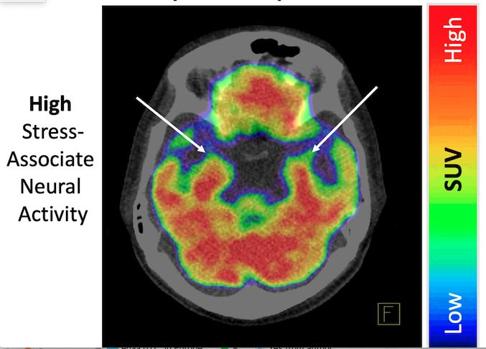

La investigación llevada a cabo en el Hospital General de Massachusetts y la Escuela de Medicina de Harvard (EE.UU.) encontró que cuanto mayor es la actividad de las células nerviosas en la región de la amígdala del cerebro, más riesgo de desarrollar el síndrome de Takotsubo.

La amígdala es la parte del cerebro que controla las emociones, la motivación, el aprendizaje y la memoria. También participa en el control del sistema nervioso autónomo y en la regulación de la función cardíaca.